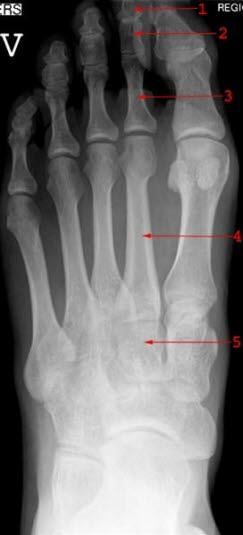

Foten består av totalt 26 bein. I bakfoten finnes hælbeinet (calcaneus) og ankelbeinet (talus). I midtfoten finnes båtbeinet (naviculare), kube-beinet (cuboideum) og tre såkalte cuneiforme-bein. Fremfoten består av fem mellomfotsbein (metatarser) og 14 tåbein (falanger). Rørknokler som metatarser og falanger har en bakre (proksimal) og en fremre (distal) ende. Den midtre delen av rørknoklene er smal og lang (skaftet), og de ytre delene er fortykkede. Den proksimale enden kalles basis, og den distale benevnes caput. Se tegninger nedenfor: